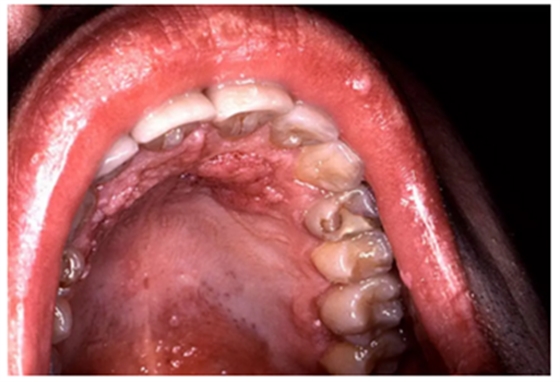

當口腔變成白色、褐色或黑色,尤其是口腔黏膜變粗糙、變厚或呈硬結(jié),意味著黏膜表皮細胞發(fā)生了變化。出現(xiàn)口腔黏膜白斑、紅斑時,很可能意味著口腔細胞已發(fā)生癌變。

1、口腔內(nèi)出現(xiàn)紅色、白色斑點